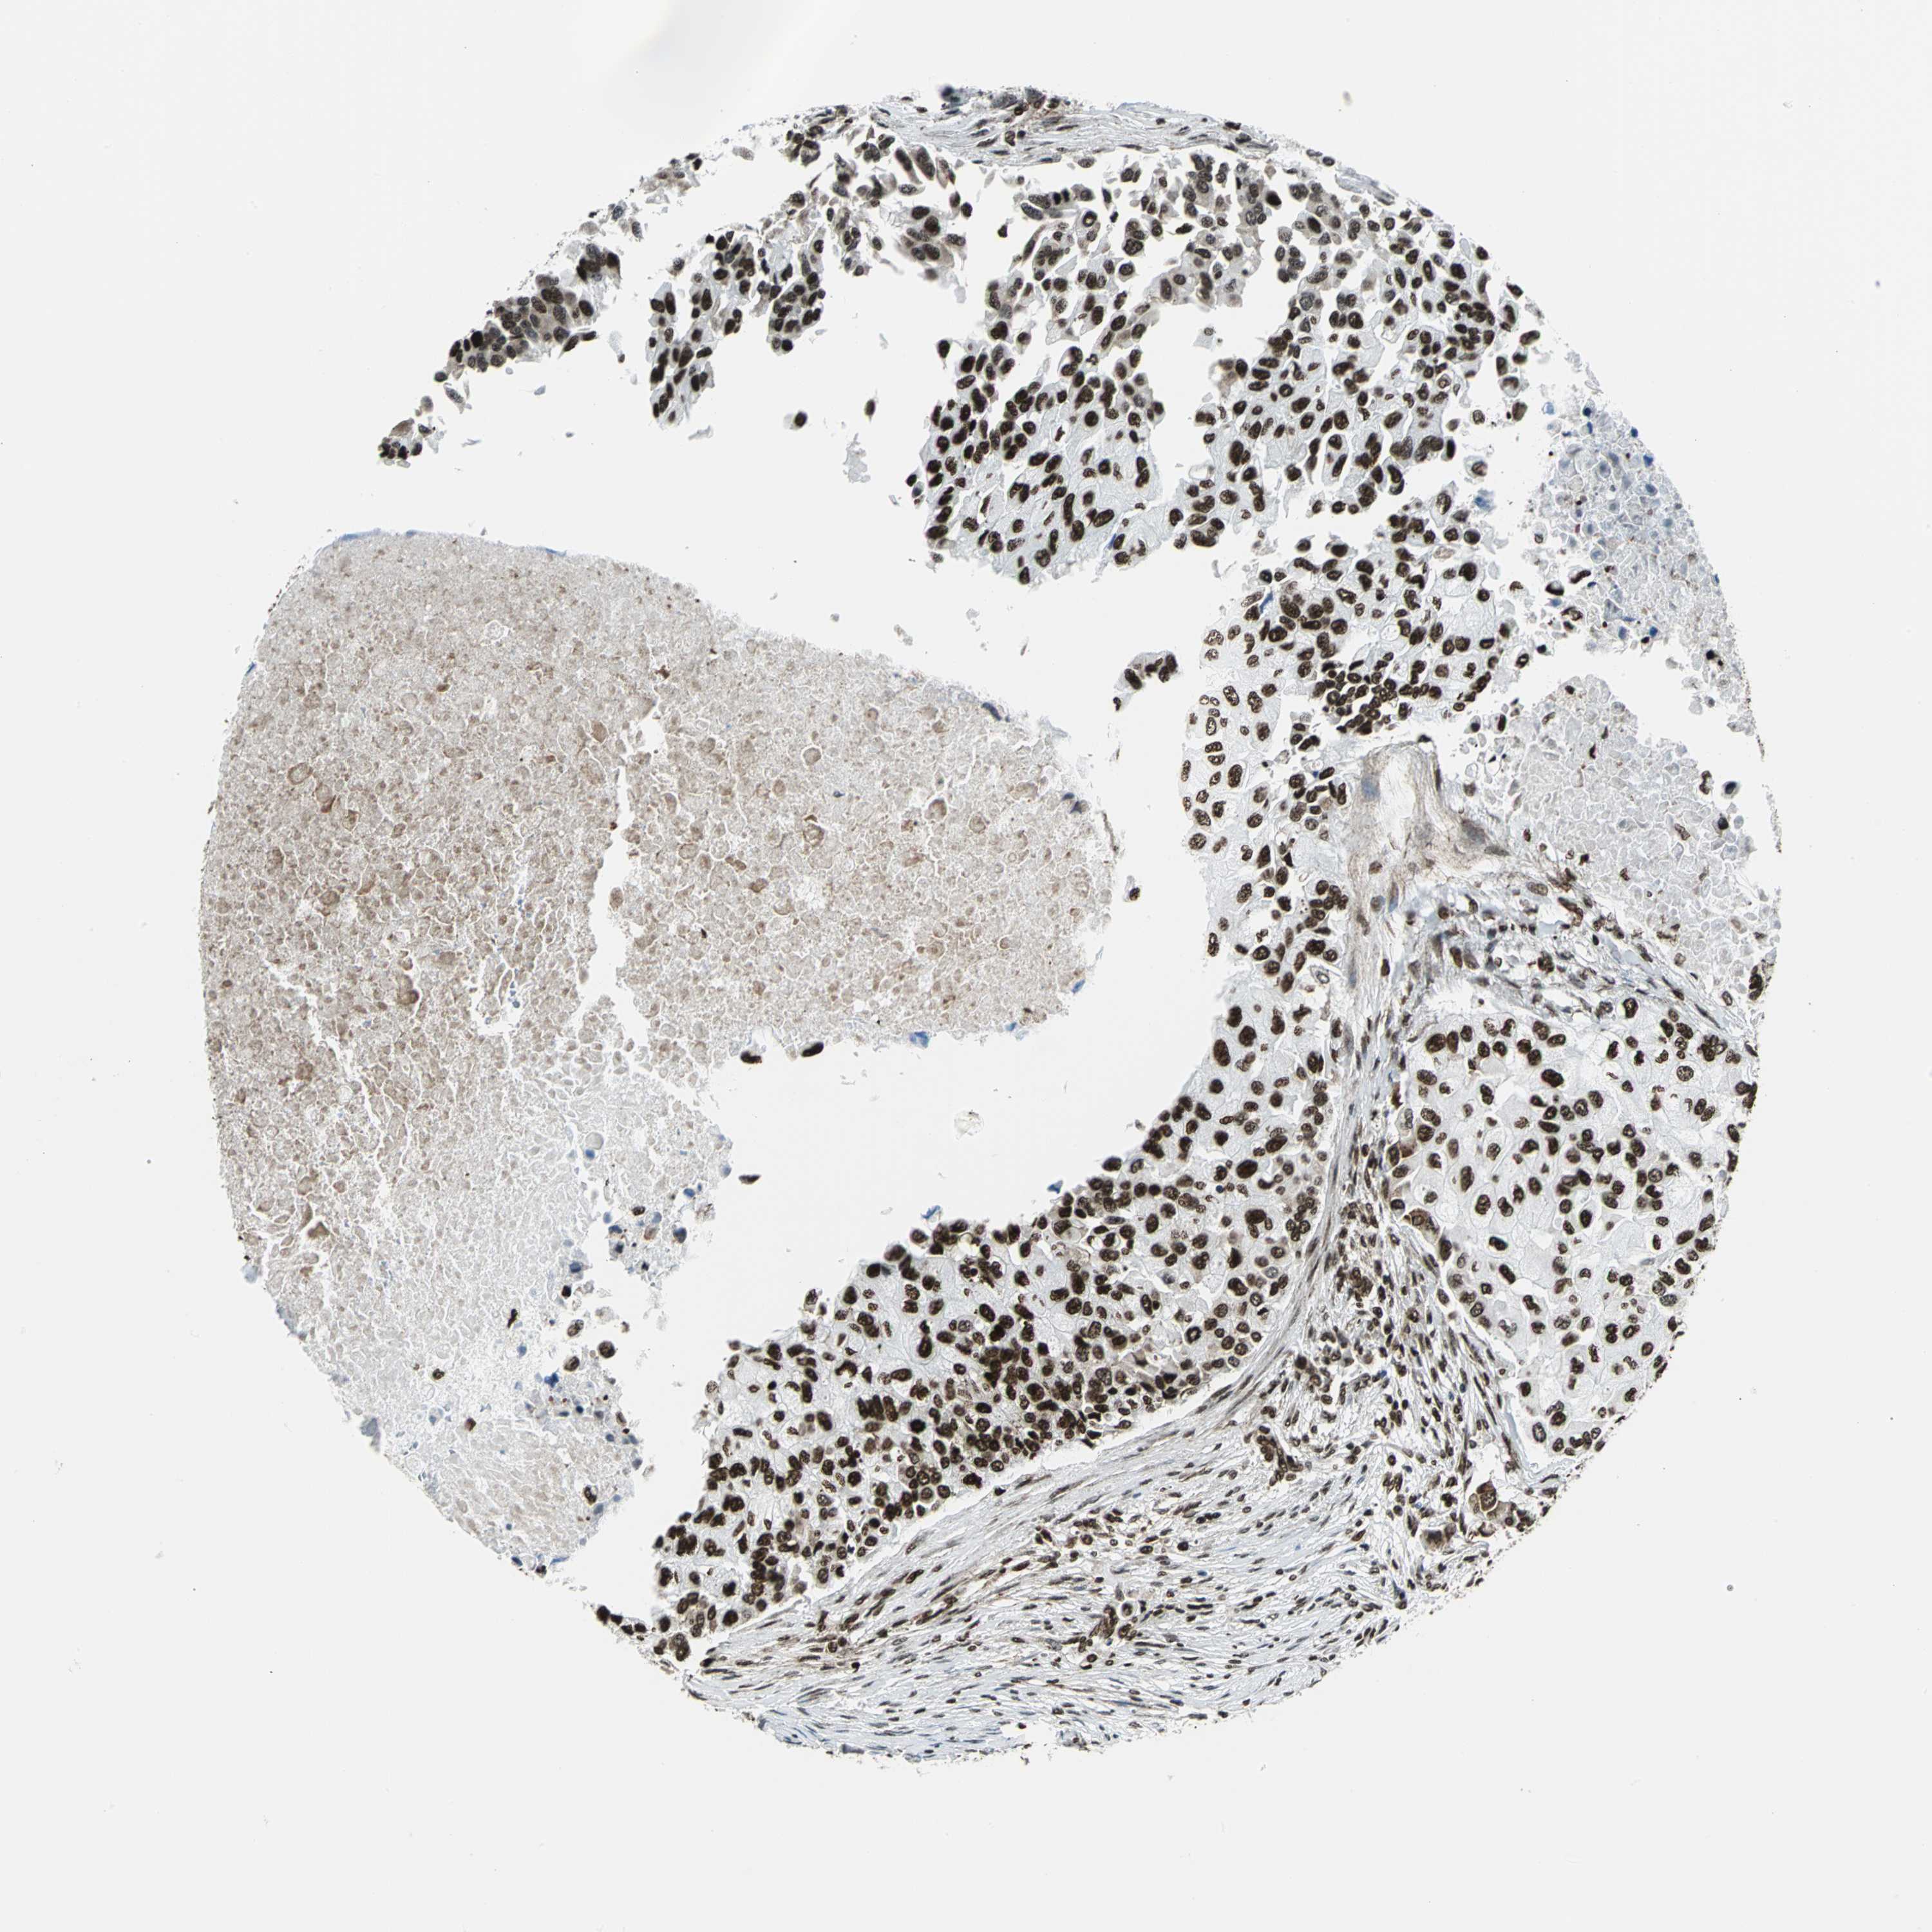

CANCER BREAST CANCER Show tissue menu

BRCA TCGA BRCA VALIDATION PROTEIN EXPRESSION

ANTIBODIES

AND

VALIDATION